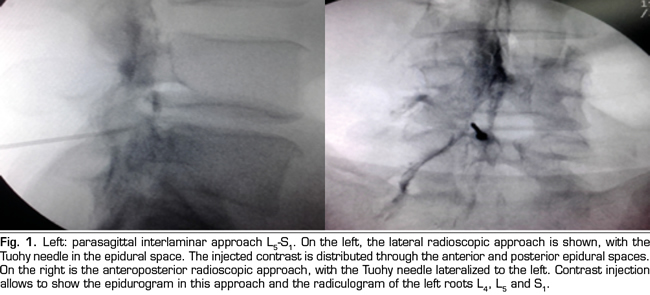

Figure 2